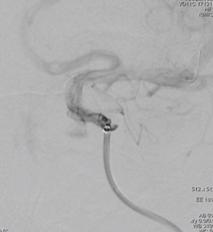

术前造影:

左侧颈内动脉C3段大动脉瘤,大小约23*11mm,瘤颈长度7.4mm,载瘤动脉远端直径约3.8mm,近端直径约4.2mm。

手术过程:

患者取仰卧位,常规消毒铺巾,Seldinger技术穿刺右侧股动脉,穿刺右股动脉,导丝引导下置入6F 90cmcook长鞘,在0.035泥鳅导丝导引下,将125cm多功能导管及6F Navien导管同轴导入左侧颈内动脉,再将长鞘跟入颈内动脉颈段。

重新行3D造影,根据目标动脉瘤及载瘤动脉选择角度,路图下在0.014 Synchro2微导丝引导下将WILLIS®覆膜支架(4.5*16mm)准确定位至左侧颈内动脉C3动脉瘤位置。

6F Navien导管超选至动脉瘤远端,微导丝引导下WILLIS®支架到位。

球囊首次扩张,支架展开,首次造影图示动脉瘤近端贴壁不良,有造影剂渗漏至动脉瘤腔内,故再次充盈球囊扩张支架近端。